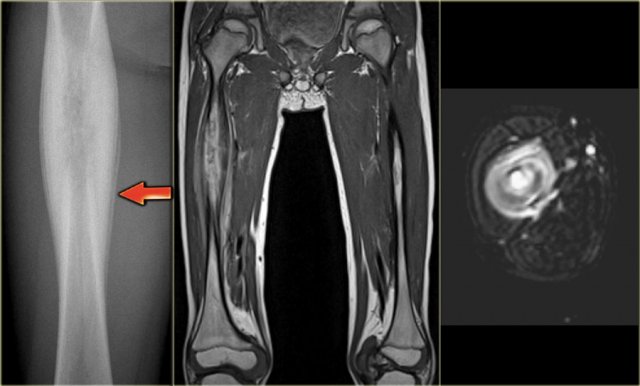

ABC versus Adamantinoma. Notice resemblance between intracortical ABC in tibia (left) and Adamantinoma (right). ABC versus Adamantinoma. Notice resemblance between intracortical ABC in tibia (left) and Adamantinoma (right).

ABC (6) - atypical case

On the left two different patients with an intracortical or subperosteal osteolytic well-defined lesion in the tibia.

The lesion on the far left was thought to be an adamantinoma because of the localisation in the anterior tibial cortex.

At biopsy it proved to be an ABC.

The image on the right is an adamantinoma.